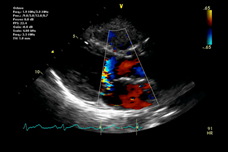

View examples of normal and abnormal echocardiograms with the Echocardiography Atlas. Access 250 annotated images and 189 videos, encompassing a wide range of cardiac pathology. Zoom and pan echocardiograms, and search for specific diseases, without the need for a network connection.

This app serves as an introductory learning tool for students or a comprehensive visual reference for cardiologists, cardiac surgeons, internists, other physicians, and sonographers.